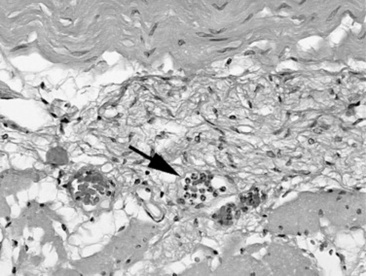

Ultrasound evaluation of horses with abdominal pain (colic) provides a rapid method to identify abnormalities within the gastrointestinal tract. Distention of the small intestine to a diameter greater than 5 cm has been strongly associated with strangulating or obstructing lesions19 (Fig. 32-11). In foals with intussusception, the small intestine appears enlarged and there is generally distended small intestine orad to the lesion; however, at the site of the intussusception there is a normal-appearing small intestinal wall (intussuscipiens) surrounded by a larger structure that appears to surround the inner small intestinal wall (called the intussusceptum)19 (Fig. 32-12). Large colon torsion occurs when the large colon rotates 360 degrees or more around the root of the mesentery to cause occlusion of venous drainage while maintaining arterial flow. This causes the wall to become thick and edematous. If ultrasound is performed in the cranioventral abdomen, just caudal to the xiphoid process, then a colon wall size greater than 9 mm is 100% specific for a large colon torsion21 (Fig. 32-13). A large colon displacement would have minimal to no vascular compromise, so it would be an ultrasound diagnosis based on exclusion. Chronic displacements did have a mild amount of edema in the colon wall, causing the size to be approximately 7 mm thick but never greater than 9 mm in the one study described.21 The colon and small intestinal wall will also become thick with inflammation. Small intestinal wall thickness greater than 4 mm is indicative of inflammation.19 The right dorsal colon can be imaged in the right tenth to twelfth intercostal space around the region of the costochondral junction, and a focal wall thickness of 9 to 12 mm has been identified with right dorsal colitis.23

image image

Fig. 32-13 Transabdominal ultrasound images of the large colon. A, In colon torsion the large colon wall is severely thick (2 cm) secondary to edema. For comparison, a normal colon wall thickness (B) should be 0.2 to 0.4 cm in thickness.